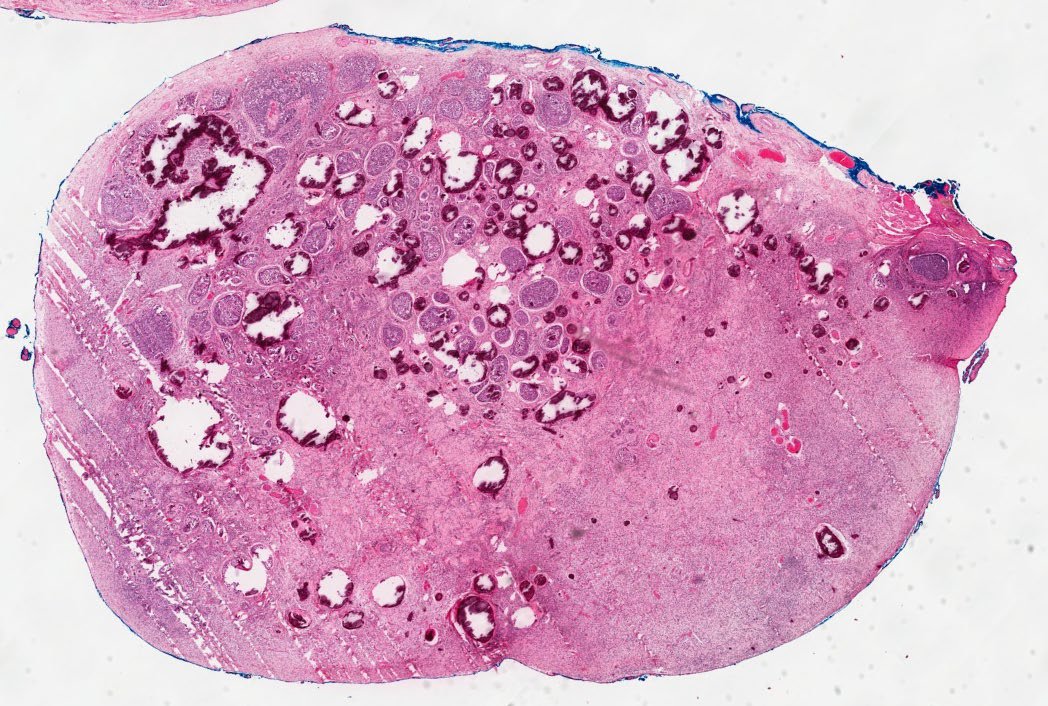

Melanoma can occur in Mucosal Sites like Rectum, Sinonasal, Vaginal Wall I always found this interesting because we usually associate it 🦀 with skin ☀️ Melanocytes are Neural Crest Derived 👶 and they migrate to the mucosa (as well as skin). #pathx #embryology #peds

Melanoma can occur in Mucosal Sites like Rectum, Sinonasal, Vaginal Wall I always found this interesting because we usually associate it 🦀 with skin ☀️ Melanocytes are Neural Crest Derived 👶 and they migrate to the mucosa (as well as skin). #pathx #embryology #peds